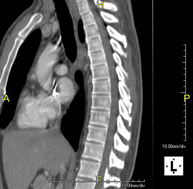

Prueba diagnóstica que consiste en el estudio de la aorta torácica (principal arteria del tórax) mediante el empleo de un equipo de TC (Tomografía Computarizada). Esta técnica requiere el empleo de contraste yodado, y proporciona imágenes de alta definición anatómica. El uso del TCMD (TC Multidetector) acorta el tiempo de exploración, disminuye la dosis de radiación y mejora la calidad de la imagen. Gracias a los múltiples detectores, en determinados estudios se puede acoplar la obtención de la imagen con el latido cardíaco, técnica que permite el estudio de la válvula aórtica y de la raíz de la arteria aorta (primeros centímetros), donde el latido del corazón suele provocar múltiples artefactos de movimiento. - Angio –TC Artèries pulmonars (estudi TEP, Tromboembòlia pulmonar)

Prova diagnòstica que consisteix en l'estudi de l'aorta toràcica (principal artèria del tòrax) mitjançant l'ús d'un equip de TC (Tomografia Computeritzada). Aquesta tècnica proporciona imatges d'alta definició anatòmica. En la majoria de casos és necessari l'ús de contrast iodat. L'ús del TCMD (TC Multidetector) escurça el temps d'exploració, disminueix la dosi de radiació i millora la qualitat d'imatge. Gràcies als múltiples detectors en determinats estudis es pot afegir l'obtenció de la imatge amb el batec cardíac, tècnica que permet l'estudi de la vàlvula aòrtica i de l'arrel de l'artèria aorta (primers centímetres), on el batec del cor acostuma a provocar falses imatges a causa del moviment. - Angio TC d'artèries pulmonars (estudi Tep, tromboembolisme)